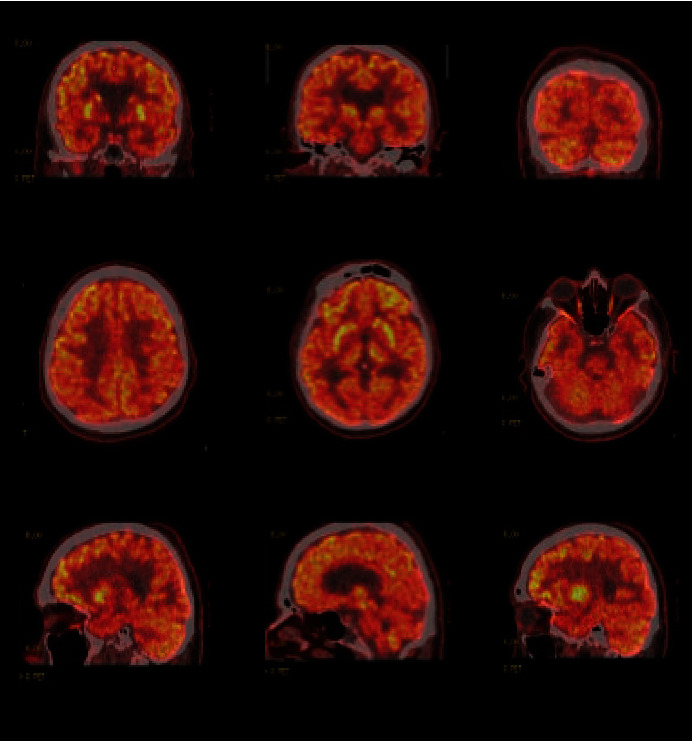

后皮质萎缩症(PCA)是一种罕见的神经退行性疾病,其特征是由于枕叶萎缩而导致主要的视觉障碍。患者在早期通常会保留认知功能,因此与其他神经认知障碍相比,诊断更为困难。在本病例中,患者主要表现为情绪症状、妄想和视幻觉。病程始于 5 年前的焦虑和失眠。随后发展为抑郁症状,包括两次自杀未遂(SA)、妄想和幻觉。通过全面的临床检查、神经心理学测试、核磁共振成像(MRI)、正电子发射断层扫描(PET)和多巴胺转运体(DAT)扫描,最终得出了诊断结果。我们的结论是,如果情绪或精神症状在晚年出现、升级或急剧变化,值得进一步检查,以评估是否存在潜在的神经退行性疾病。

Posterior cortical atrophy (PCA) is a rare neurodegenerative disorder characterized by predominant visual deficits due to its atrophy of the occipital lobes. Patients typically have preserved cognitive function during the early stages, making diagnosis more difficult when compared to other neurocognitive disorders. In this case, the patient presented predominantly with mood symptoms, delusions, and visual hallucinations. The disease course began 5 years ago with anxiety and insomnia. It developed into depressive symptoms including two suicide attempts (SAs), paranoia, and hallucinations. The diagnosis was eventually reached utilizing a thorough clinical exam, neuropsychological testing, MRI, positron emission tomography (PET), and dopamine transporter (DAT) scans. We conclude that mood or psychotic symptoms that emerge, escalate, or change dramatically at later ages merit further workup to evaluate for underlying neurodegenerative disorders.